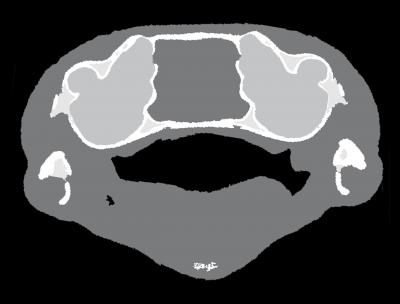

The next step was to identify the mechanism by which these seemingly deaf frogs were able to hear sound. Various mechanisms have been proposed: an extra-tympanic pathway through the lungs, muscles which in frogs connect the pectoral girdle to the region of the inner ear, or bone conduction. "Whether body tissue will transport sound or not depends on its biomechanical properties. With X-ray imaging techniques here at the ESRF, we could establish that neither the pulmonary system nor the muscles of these frogs contribute significantly to the transmission of sound to the inner ears", says Peter Cloetens, a scientist at the ESRF who took part in the study. "As these animals are tiny, just one centimetre long, we needed X-ray images of the soft tissue and the bony parts with micrometric resolution to determine which body parts contribute to sound propagation."

Numerical simulations helped to investigate the third hypothesis, that the sound was received through the frog's heads. These simulations confirmed that the mouth acts as a resonator, or amplifier, for the frequencies emitted by this species. Synchrotron X-ray imaging on different species showed that the transmission of the sound from the oral cavity to the inner ear has been optimized by two evolutionary adaptations: a reduced thickness of the tissue between the mouth and the inner ear and a smaller number of tissue layers between the mouth and the inner ear. "The combination of a mouth cavity and bone conduction allows Gardiner's frogs to perceive sound effectively without use of a tympanic middle ear", concludes Renaud Boistel.